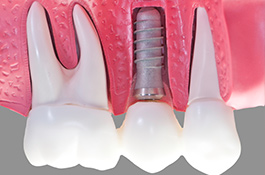

Als Implantat bezeichnet man in der Zahnmedizin eine künstliche Zahnwurzel, die nach Verlust eines eigenen Zahnes als Ersatz eingebracht wird. Das Implantat dient als Basis bzw. Verankerung einer festsitzenden Krone. Geht nur ein Zahn verloren, dient das Implantat zum Schluss der Lücke, ohne dass eine Brücke angefertigt werden muss und dafür die vielleicht intakten Nachbarzähne abgeschliffen werden. Damit schonen wir die umgebenden Zähne. Spätfolgen des Zahnverlustes, wie Kiefergelenkprobleme, Zahnwanderungen oder Karies können vermieden werden. Sind bereits mehrere Zähne verloren gegangen, die nur durch eine Teil- oder Vollprothese ersetzt werden können, ermöglichen wir durch das Einbringen mehrerer Implantate wieder einen festsitzenden Zahnersatz.

Implantate bestehen aus dem körperverträglichen und langlebigen Metall Titan. In einem minimalinvasiven operativen Eingriff setzen wir das Implantat in den Knochen ein. Die speziell bearbeitete Oberfläche garantiert ein zügiges Einheilen und das feste Verwachsen mit dem umgebenden Knochengewebe. Implantate können darüber hinaus den gefürchteten Knochenschwund in zahnlosen Kieferabschnitten verhindern oder verzögern. Den eigenen Zahnwurzeln ähnlich, übertragen Implantate die Kaukräfte auf den Kieferknochen. Dieser Trainingseffekt ist ein wichtiger Reiz für den Erhalt des Knochen- und Stützgewebes. Deshalb sollten Implantate möglichst bald nach dem Verlust oder Entfernen eines Zahns verankert werden.